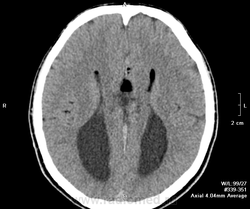

Дермоид головного мозга.

Однажды я представляла дермоид http://www.radiomed.ru/cases/dermoid-golovnogo-mozga

Вот еще один

А на прорыв кисты в желудочки и субарахноидально обратили внимание?

"Слона-то я и не приметил"-я насчет мозолистого тела.Сразу не обратила внимание-у меня все желудочки на уме.Но потом поняла, что чего-то не хватает.

Nela wrote:

А прорыв хорошо виден на 3 скане?

Почти на всех сканах видно, что жир (самое черное) в субарахноидальных щелях и в желудочках. Вечером покажу стрелками. Сейчас убегаю.